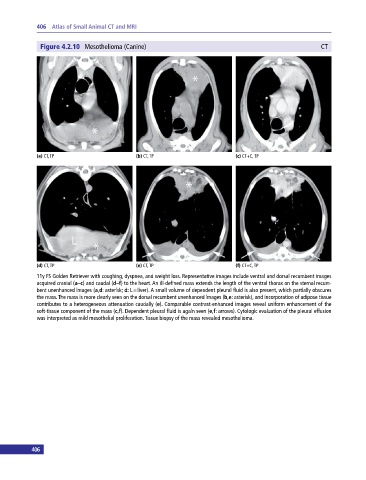

Figure 4.2.10 Mesothelioma (Canine) CT

(a) CT, TP (b) CT, TP (c) CT+C, TP

(d) CT, TP (e) CT, TP (f) CT+C, TP

11y FS Golden Retriever with coughing, dyspnea, and weight loss. Representative images include ventral and dorsal recumbent images

acquired cranial (a–c) and caudal (d–f) to the heart. An ill‐defined mass extends the length of the ventral thorax on the sternal recum-

bent unenhanced images (a,d: asterisk; d: L = liver). A small volume of dependent pleural fluid is also present, which partially obscures

the mass. The mass is more clearly seen on the dorsal recumbent unenhanced images (b,e: asterisk), and incorporation of adipose tissue

contributes to a heterogeneous attenuation caudally (e). Comparable contrast‐enhanced images reveal uniform enhancement of the

soft‐tissue component of the mass (c,f). Dependent pleural fluid is again seen (e,f: arrows). Cytologic evaluation of the pleural effusion

was interpreted as mild mesothelial proliferation. Tissue biopsy of the mass revealed mesothelioma.